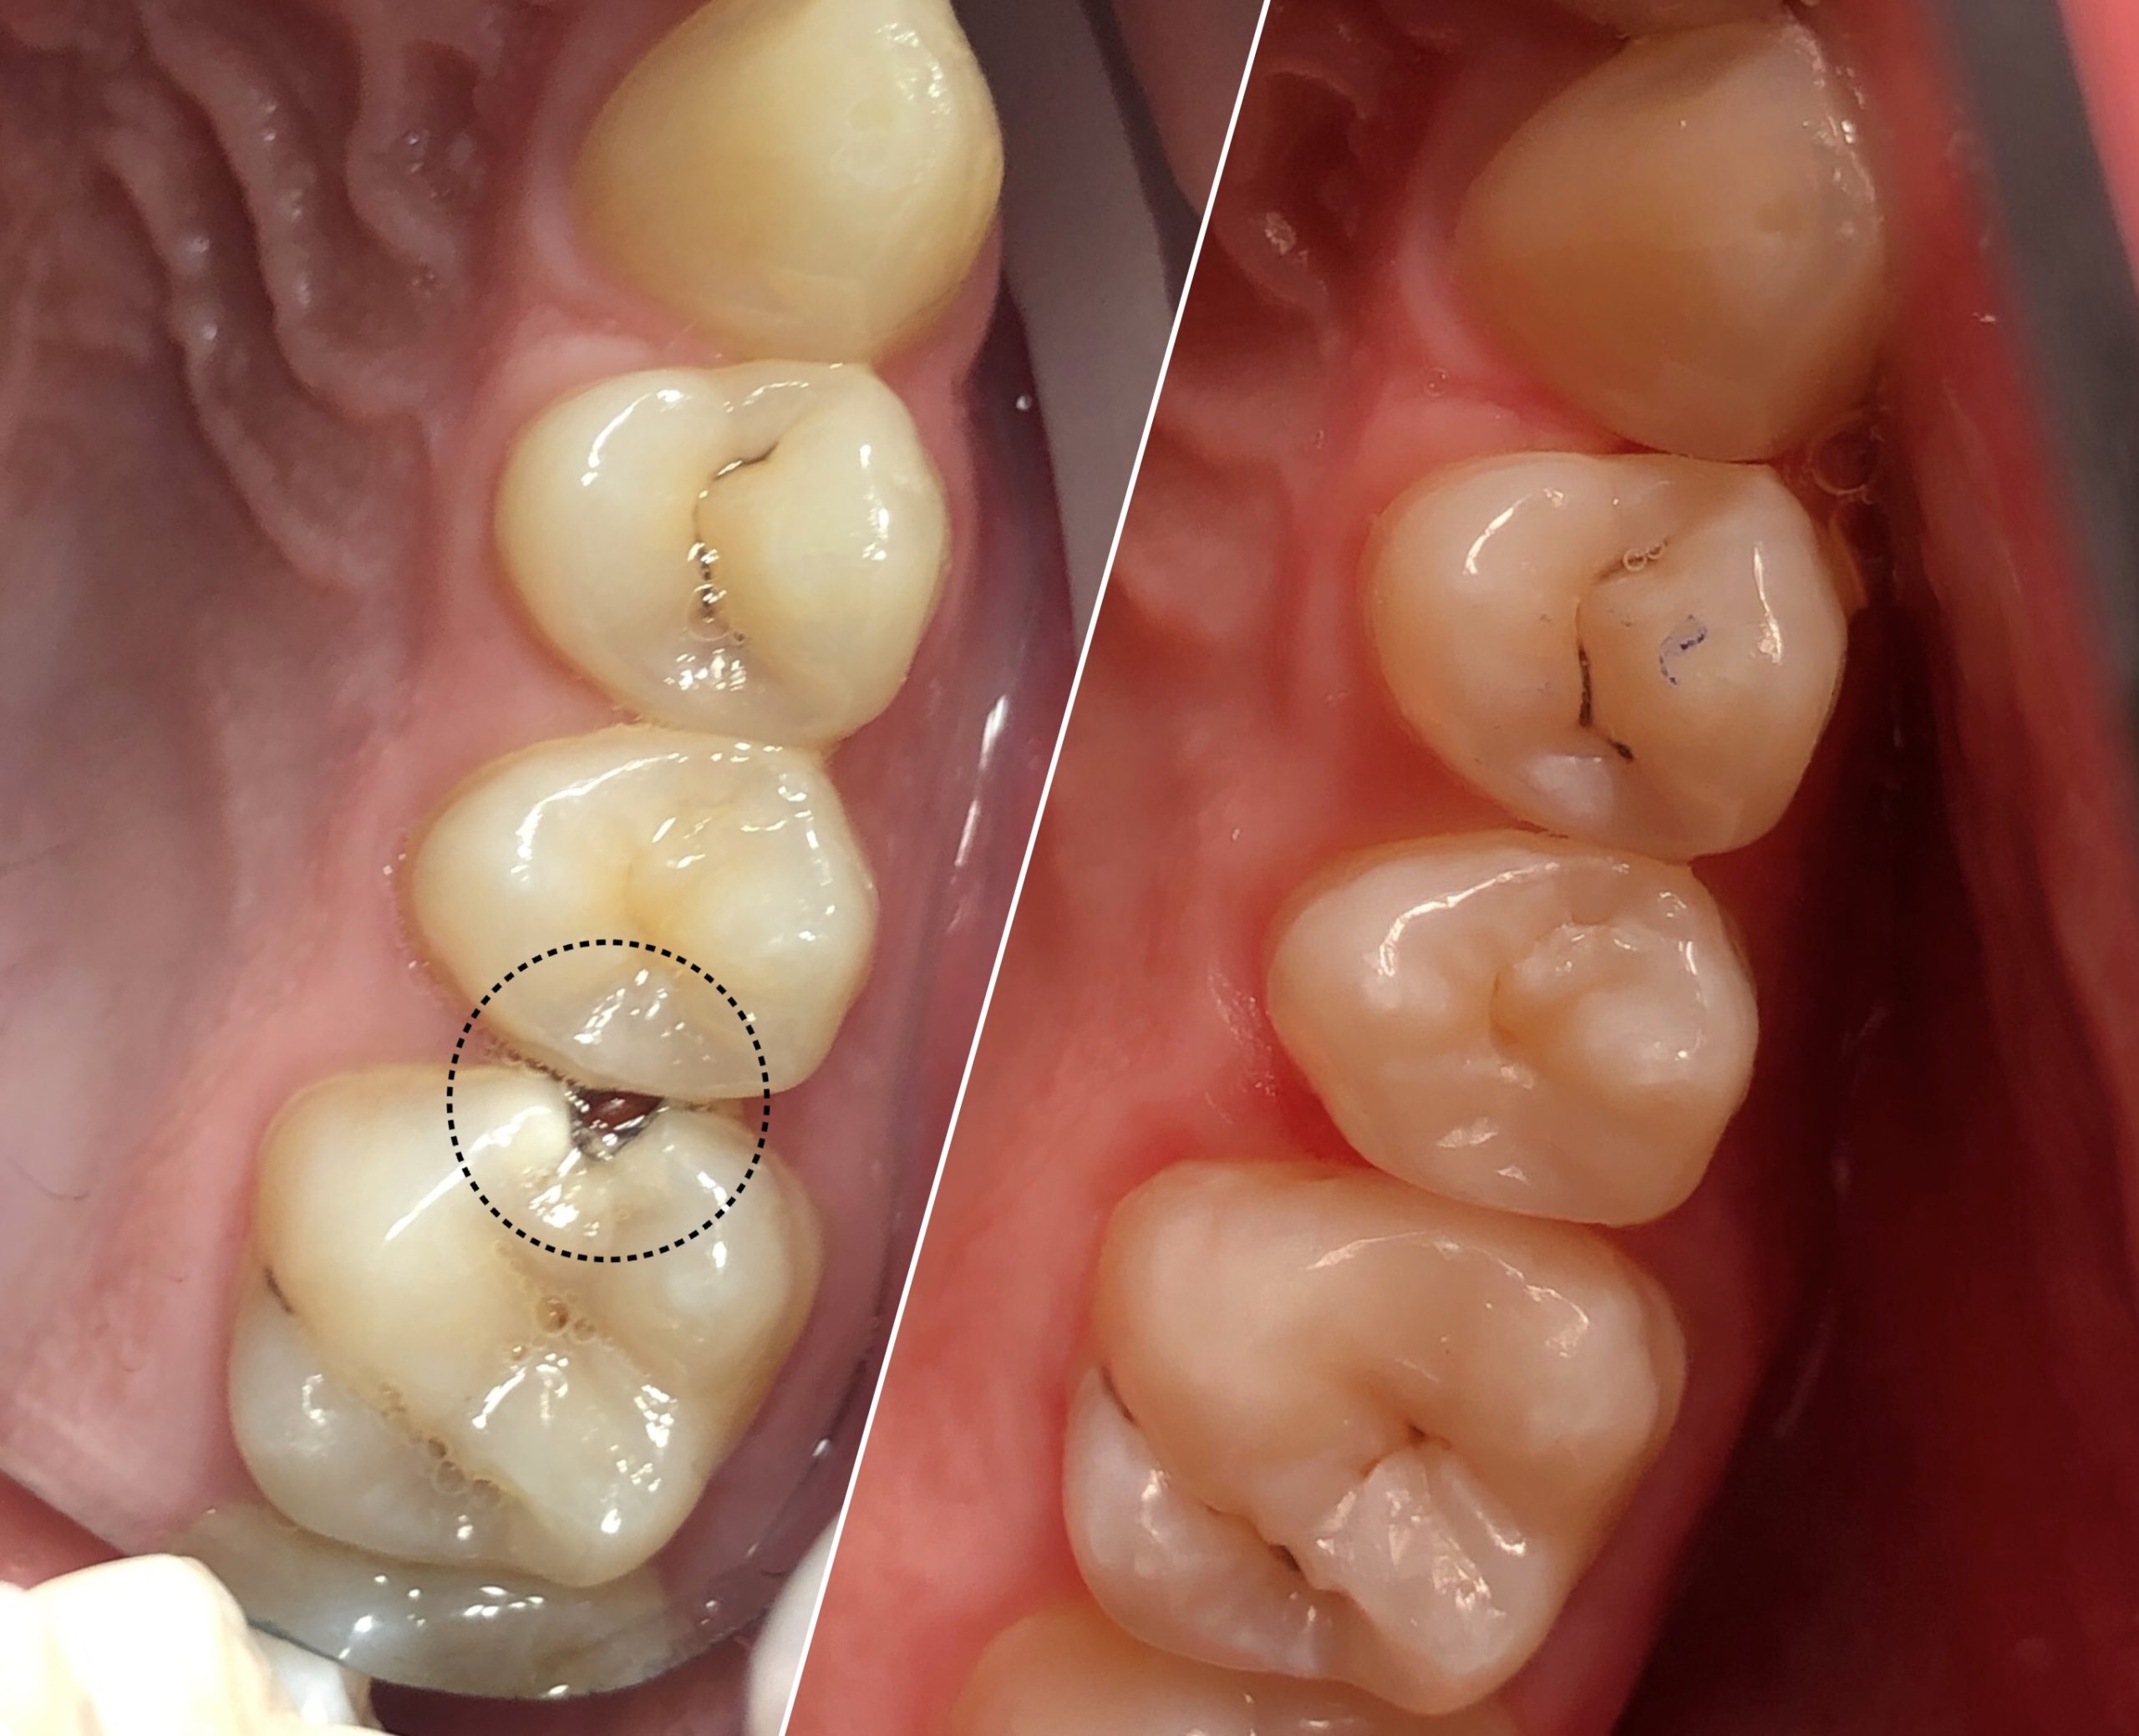

• Диагностика и лечение кариеса и его осложнений (пульпиты, периодонтиты)

• Художественная реставрация фронтального и бокового участка зубов